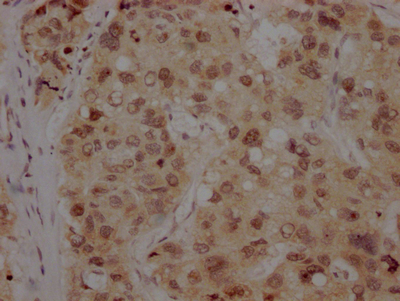

IHC image of CSB-RA916472A0HU diluted at 1:100 and staining in paraffin-embedded human liver cancer performed on a Leica BondTM system. After dewaxing and hydration, antigen retrieval was mediated by high pressure in a citrate buffer (pH 6.0). Section was blocked with 10% normal goat serum 30min at RT. Then primary antibody (1% BSA) was incubated at 4℃ overnight. The primary is detected by a Goat anti-rabbit IgG polymer labeled by HRP and visualized using 0.05% DAB.

IHC image of CSB-RA916472A0HU diluted at 1:100 and staining in paraffin-embedded human lung cancer performed on a Leica BondTM system. After dewaxing and hydration, antigen retrieval was mediated by high pressure in a citrate buffer (pH 6.0). Section was blocked with 10% normal goat serum 30min at RT. Then primary antibody (1% BSA) was incubated at 4℃ overnight. The primary is detected by a Goat anti-rabbit IgG polymer labeled by HRP and visualized using 0.05% DAB.